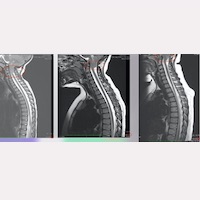

終絲系統®醫療法病例介紹:Chiari 畸形第一型患者小腦扁桃體下疝回升康復。

閱讀更多 »

2023年10月6日